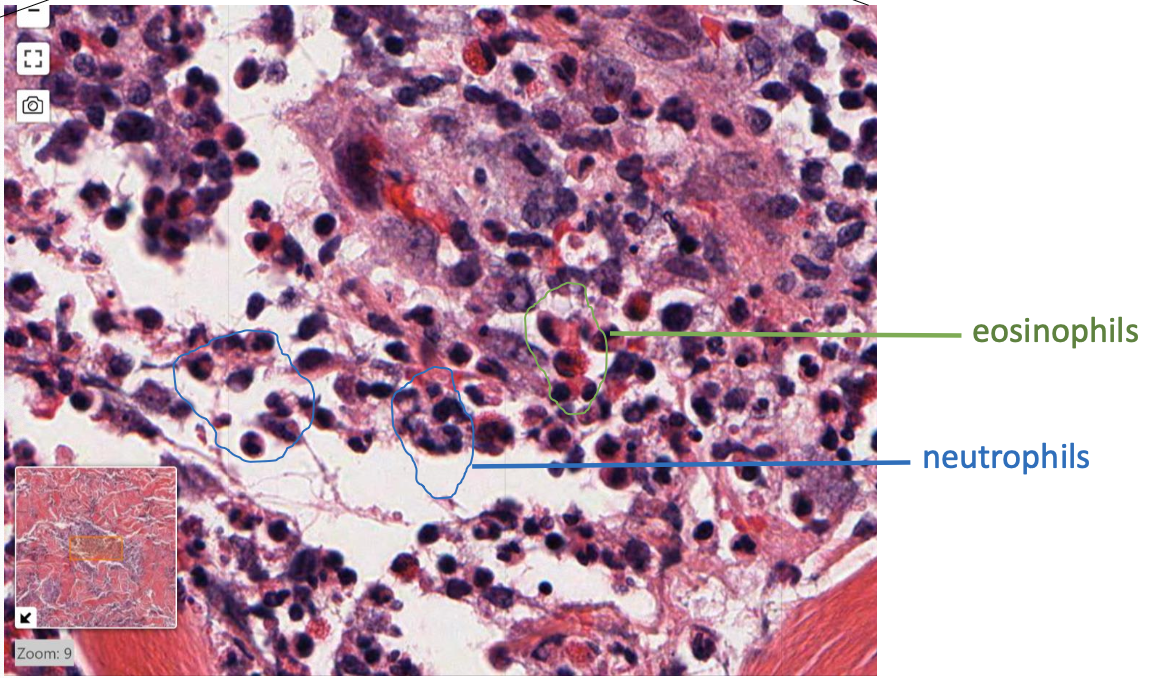

what type of cells do you see?

neutrophils!

messy appearance of cells

nucleus of many cells have multi-lobed appearance

when you see neutrophils, what type of inflammatory response is happening?

acute inflammation

normal or abnormal? localized or diffuse?

abnormal, diffuse